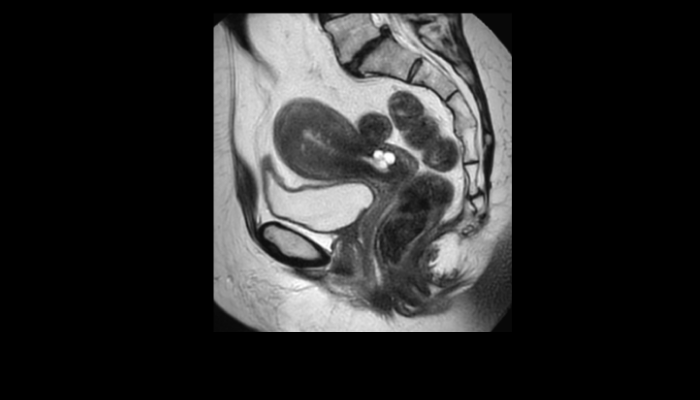

頭部MRI画像 頭部MRI脳腫瘍や脳梗塞、認知症など脳の病気を詳細に評価します。 MRA画像 頭部MRA造影剤を使わずに脳の動脈を描出します。動脈瘤や狭窄を検索します。 脊椎MRI画像 脊椎MRI椎間板ヘルニアや脊柱管狭窄症など脊椎や脊髄の疾患を評価します。 腹部MRI画像 上腹部MRI・MRCP肝臓・胆のう・膵臓・腎臓などの上腹部の重要臓器を詳細に評価します。 乳房MRI画像 乳腺MRIマンモグラフィや超音波と併せて、乳がんを検索や病変の範囲を評価します。 前立腺MRI画像 前立腺MRI前立腺がんを検索します。PSA高値の方はまず前立腺MRIをお勧めします。 子宮・卵巣MRI画像 子宮・卵巣子宮筋腫や子宮体癌、卵巣腫瘍など女性特有の病気を評価します。 膝関節MRI画像 膝関節膝関節の骨や靭帯、半月板を評価します。靭帯断裂や半月板損傷などレントゲンでは評価できない構造も診断できます。 肩関節MRI画像 肩関節肩関節の骨や腱、靭帯を評価します。腱板断裂や腱の断裂などレントゲンでは評価できない構造も診断できます。 心臓MRA 心臓MRA狭心症、心筋梗塞の原因となる冠動脈の狭窄を評価します。造影剤を使用せず、撮影可能です。 DWIBS画像 DWIBS全身のがんを広く検索します。リンパ節や転移の評価にも優れます。